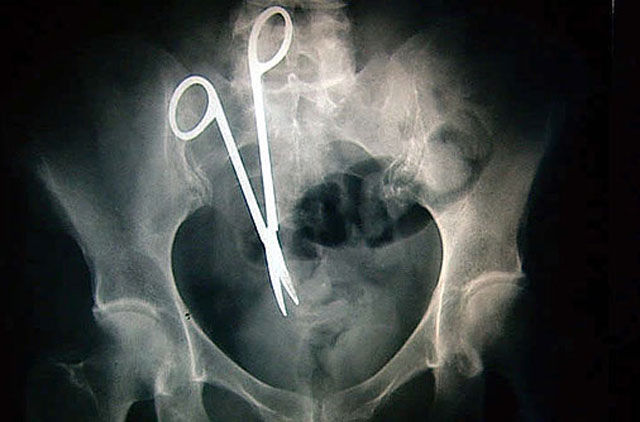

This guy was picking his teeth with a pair of scissors and then started laughing and down go the scissors. He lived and is fine!

X-ray of scissors left inside Pat Skinner's stomach of Hurstvlle during a operation at St George Hospital, Sydney